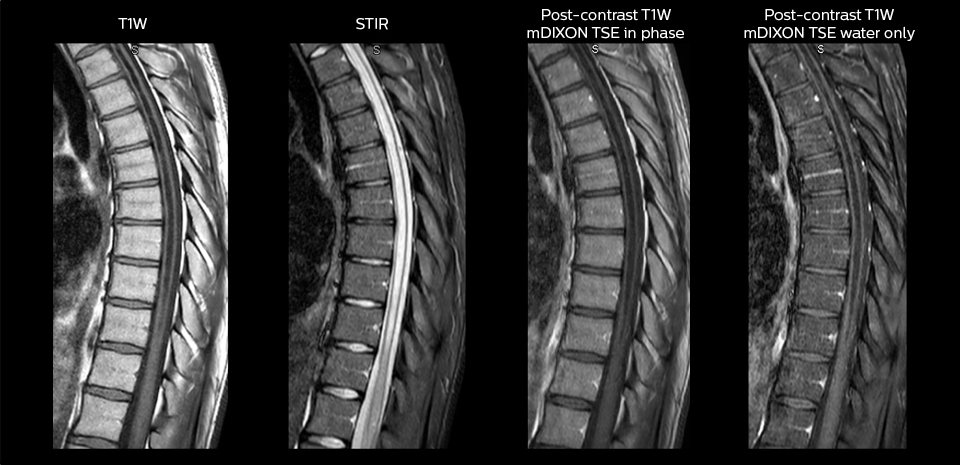

Including mDIXON TSE for robust fat suppression

“We use mDIXON TSE extensively in our spine imaging in the emergency room,” says Dr. Karis. “It’s particularly nice in that it is very robust with regard to susceptibility type of problems that would come up with traditional spectral fat-saturated images; these problems are essentially eliminated with the mDIXON technique. In our ED environment it’s really nice to have the fat-free imaging that goes along with the mDIXON technique.

“For the thoracic and cervical spine routine non-contrast exam, for example, we perform one mDIXON T2 TSE sequence, which provides us with two outputs: the fat-and-water-together T2-weighted images, as well as the water-only sagittal T2-weighted images. And then we also perform an axial gradient echo exam.”

To minimize the time taken to perform scans, rapid MRI examination protocols (ExamCards) were developed, shortening the total scanning time to even less than 10 minutes in some exams. Techniques like mDIXON (modified DIXON) are used for robust capturing of fat-free MRI images in a hectic ED environment.

in image acquisition and postprocessing algorithms.”“mDIXON TSE sequences allow simultaneous characterization of morphological changes from the in-phase T2-weighted images and visualization of edematous changes, thanks to the water T2-weighted images from the same acquisition. Anatomical and morphological considerations could be a partial or complete ligament tear, a bony avulsion or hematoma.”

“mDIXON TSE sequences allow simultaneous characterization of morphological changes from the in-phase T2-weighted images and visualization of edematous changes, thanks to the water T2-weighted images from the same acquisition. Anatomical and morphological considerations could be a partial or complete ligament tear, a bony avulsion or hematoma.”